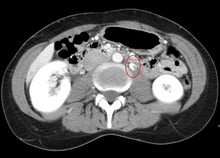

Thrombosis in the left renal vein associated with dilation.